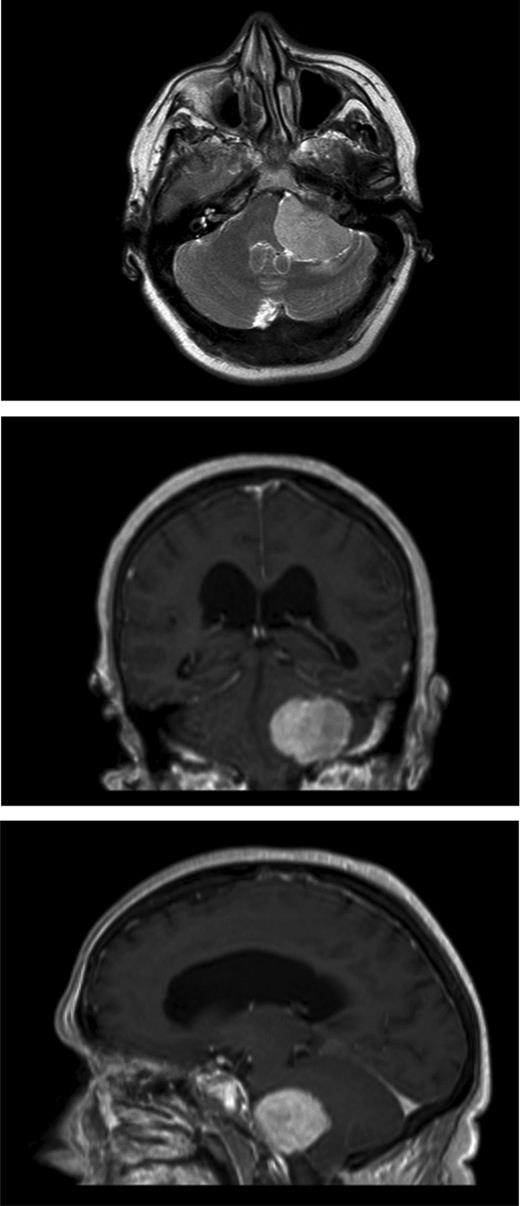

Magnetic resonance imaging (MRI) head confirmed the presence of a primary posterior cranial fossa meningioma that was surrounding the jugular foramen, compressing the brainstem and vagus nerve (Fig. 2).